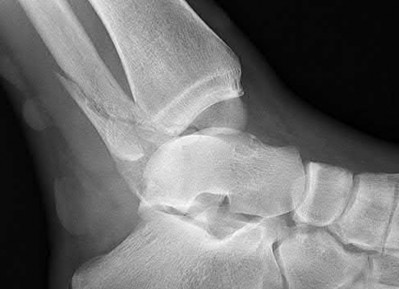

Question 2

A 28-year-old male sustains a severe hyper-dorsiflexion injury to his ankle in a motor vehicle accident, resulting in a Hawkins Type III talar neck fracture. Which of the following arteries provides the predominant blood supply to the body of the talus, placing it at significant risk for avascular necrosis in this injury?

Explanation

The artery of the tarsal canal, which is a branch of the posterior tibial artery, provides the dominant blood supply to the talar body. In a Hawkins Type III fracture (talar neck fracture with subtalar and tibiotalar dislocation), the blood supply from the artery of the tarsal canal, the artery of the sinus tarsi, and capsular vessels are disrupted, leading to an avascular necrosis (AVN) rate approaching 100%.